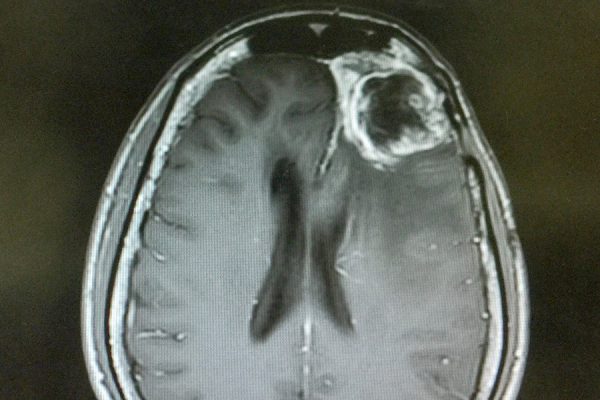

Origin Cells of Glioblastoma May Have Been Identified

“Pink Drink” to Aid Brain Tumor Treatment